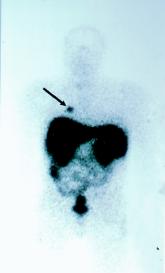

ArticleOctreotide Scan for CarcinoidsAuthor:M. Edmonds, MD, FRCPC, FACPPublish date: October 11, 2006Read More